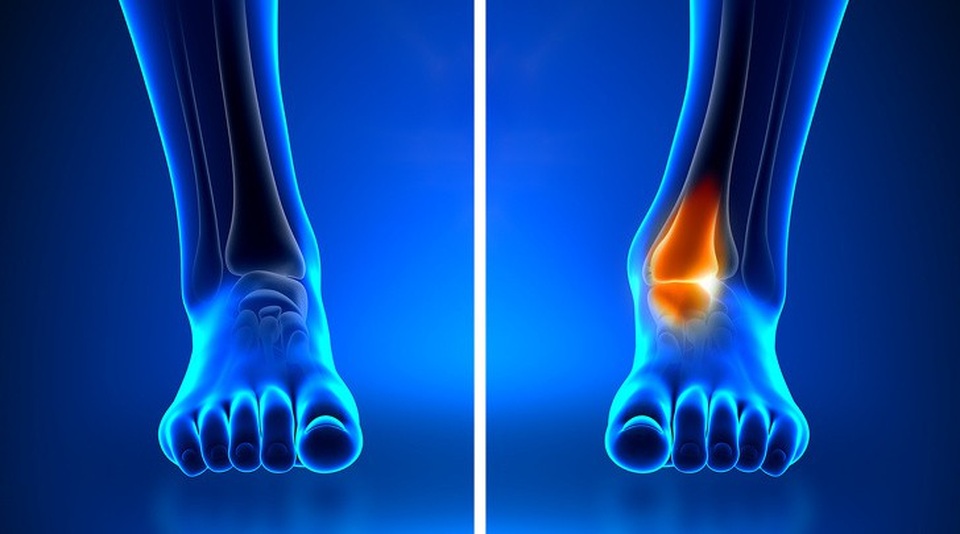

8. Chân biến dạng

Chân có hiện tượng cong vào trong hoặc một sự thay đổi về hình dạng có thể là nguyên nhân của việc mang giày cao gót quá lâu và thường xuyên, dẫn tới sự phân bố tải trọng không đều, dồn tải về khu vực vòm ngang của bàn chân. Khi khu vực này bị quá tải, bàn chân sẽ cảm thấy đau nhức, khó chịu và dẫn tới sự thay đổi về hình dạng.